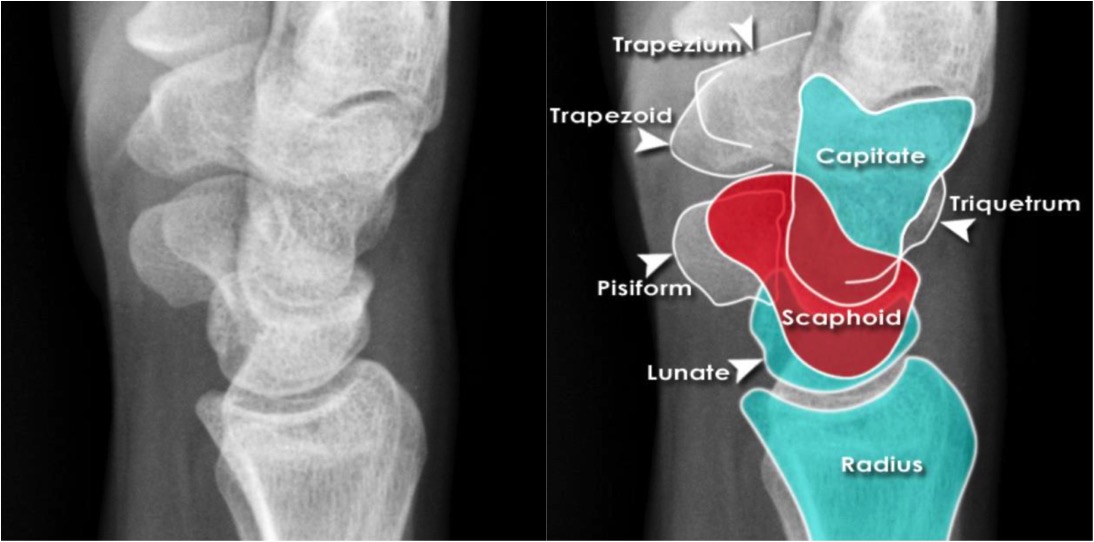

Wrist Radiographic Anatomy Radiology student, Radiology, Radiology